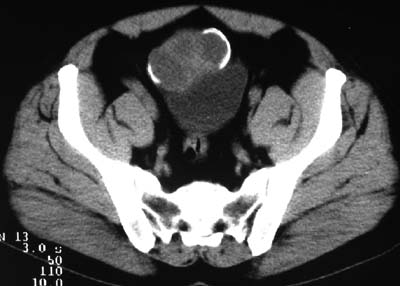

二、男,55岁,排尿困难两年,b超示盆腔不均质包块,ct值约27hu.

第二例可能为脐尿管肿瘤。

例2:盆腔占位,肿块密度欠均匀,其内有钙化影,其边界清晰,膀胱前上壁受压,膀胱壁尚清晰,考虑为不典型畸胎瘤压迫膀胱可能,建议增强扫描吧。

病例1;畸胎瘤,子宫肌瘤。病例2,与膀胱关系密切,脐尿管癌?

1.盆腔畸胎瘤

2.考虑脐尿管肿瘤

1典型盆腔畸胎瘤.2考虑脐尿管类肿瘤,建议增强扫描.

病例1,盆腔畸胎瘤并子宫肌瘤;病例2,囊性肿块,周围有壳状钙化,膀胱受压改变,考虑:脐尿管囊肿并感染,畸胎瘤?

1盆腔畸胎瘤伴子宫肌瘤2 第二例可能为脐尿管肿瘤。